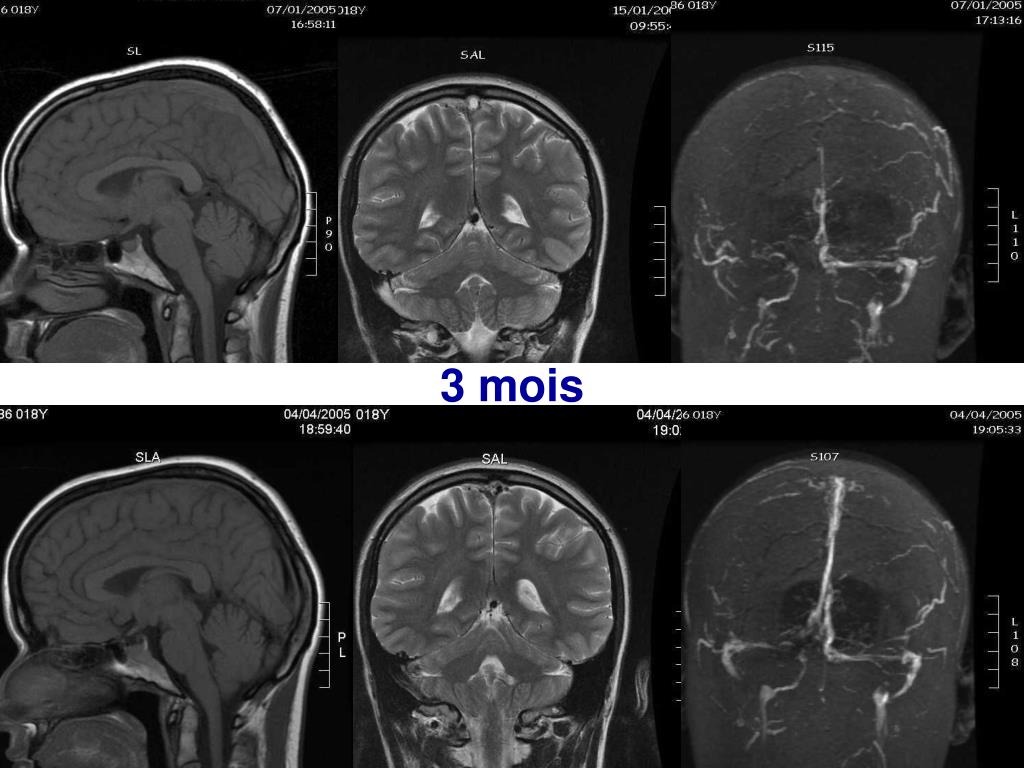

39. 3 mois